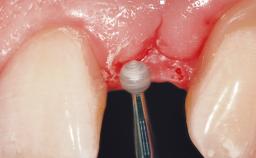

Late Placement of an Implant in a Maxillary Left Central Incisor Site

A 30-year-old female patient had lost tooth 21 and was referred to our clinic for consultation and treatment. Due to advanced apical infection, tooth 21 had been extracted two months earlier at another clinic and an acrylic-resin tooth had been bonded to the adjacent teeth. The patient desired implant treatment to avoid any damage to the adjacent natural teeth. While the patient had no history of any systemic disorder, she was a heavy smoker and exhibited medium to advanced periodontitis in the entire jaw. After the initial treatment to achieve a pocket probing depth of less than 4 mm and no bleeding on probing, a decrease in the height of the papillae mesial and distal to the extraction site and overall gingival recession were observed.